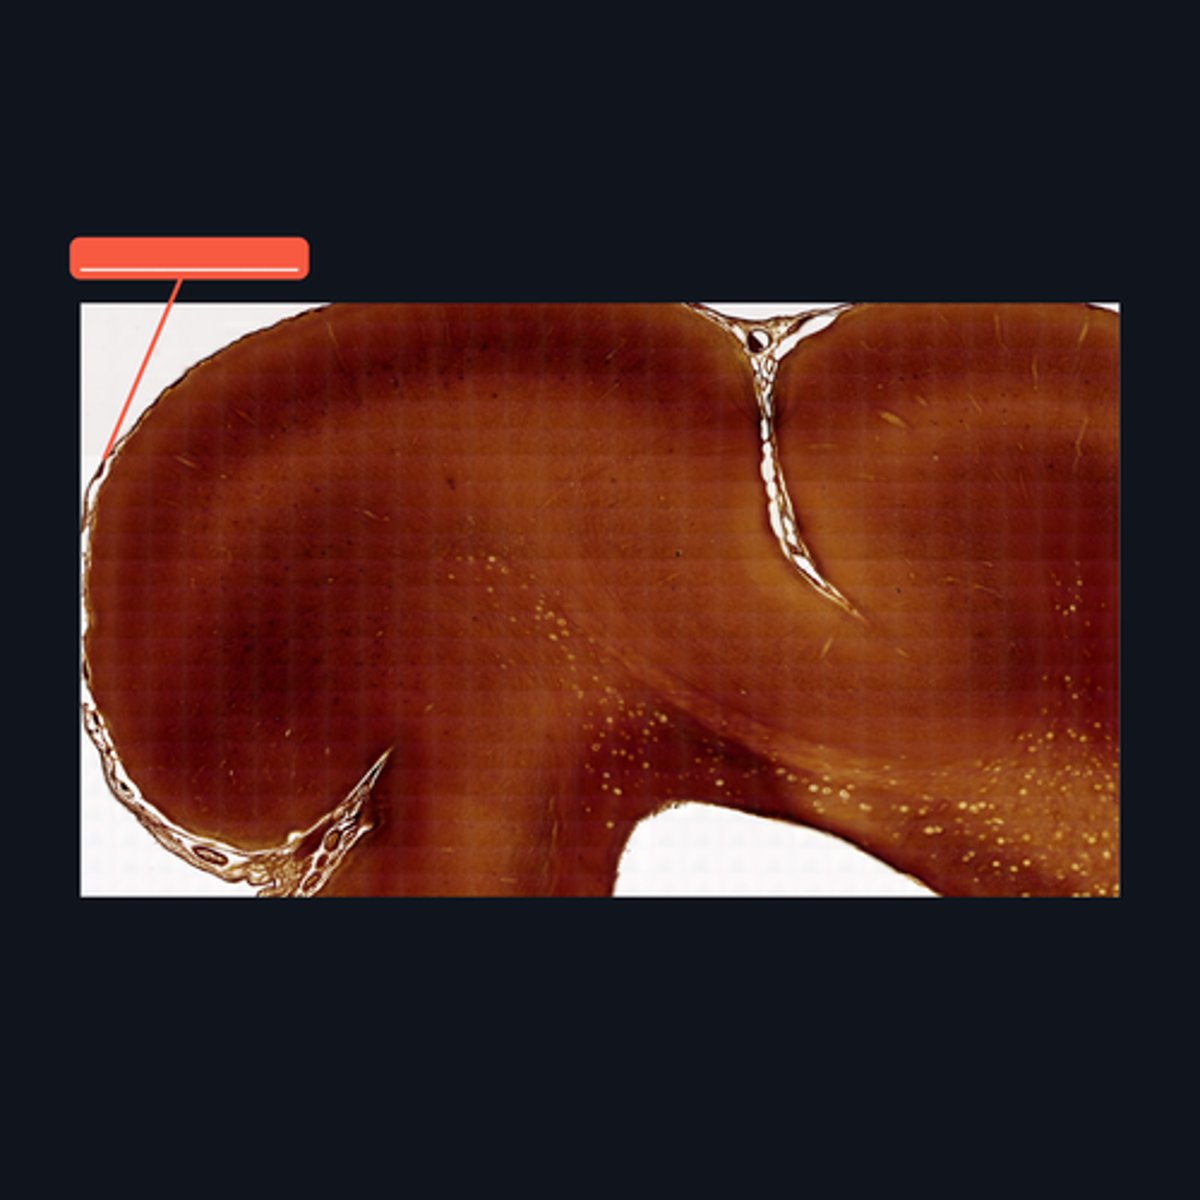

Gray Matter

Identify the pointed region in the spinal cord

(1) Ventral Horn, (2) Dorsal Horn

Identify the pointed regions of the gray matter of the spinal cord

Gray Matter (When looking at speciemen from the brain, all areas in the periphery are considered Gray Matter)

Identify the pointed region in the Cerebellum